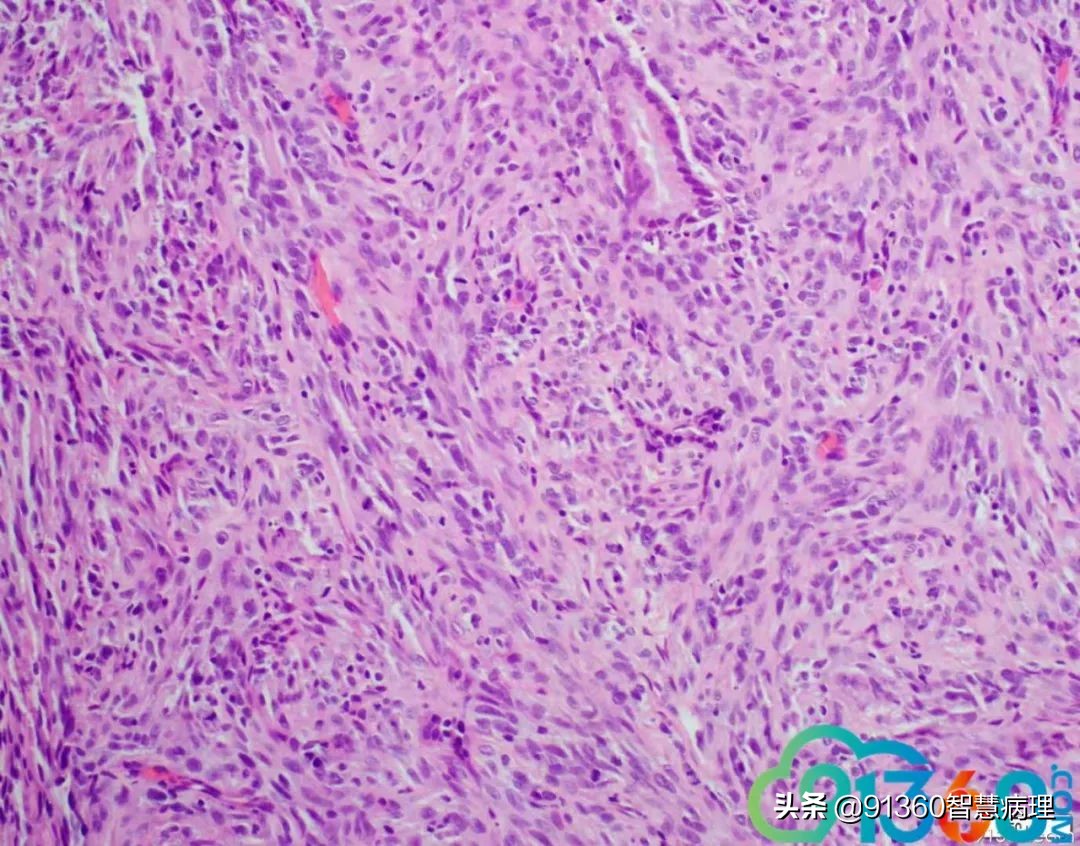

邢德印 39岁,宫颈活检 石岩 腺肉? 任永昌 梭形细胞恶性肿瘤,肉瘤首考,肉瘤样癌次之! 郭晓静 @邢德印(妇科病理)邢老师, 周末好!您的病例肯定有难度谢谢分享!抛砖引玉,我说下自己看法。1.39岁,为什么要活检?hpv情况和液基肯定有问题2.低倍这一点给我的感觉是有异型,其他很多似乎很弥漫,没有找到鳞状上皮,梭形细胞样

邢德印 Desmin -Sarcomatoid carcinoma; spindle cell carcinoma 石岩 @邢德印(妇科病理) 好例子 邢德印 以前没见过这么明显的,太肉瘤样了 任永昌 @邢德印(妇科病理) 赞 郭晓静 @邢德印(妇科病理) 我偏向猜的答案也是这个,。谢谢分享! 王昀 @邢德印(妇科病理) 好例子,没见过这么弥漫肉瘤样的,回过头来看,好像还是有点结构的样子

邢德印 @王昀 301 圈里的是mitosis 任永昌 @邢德印(妇科病理) @王昀 301 实际上,上边这个腺体有异型,核过于大。

王昀 哦,我说那个裂隙,有点像腺的结构 邢德印 @临沂市中心医院任永昌 @王昀 301 腺体其实是entrapped,正常的腺体 王昀 我是想起乳腺的化生性癌,所以想看看有没有腺和梭形细胞过渡移行的地方,能找点线索,可能是知道答案后开始想象了,这个可能是假腺